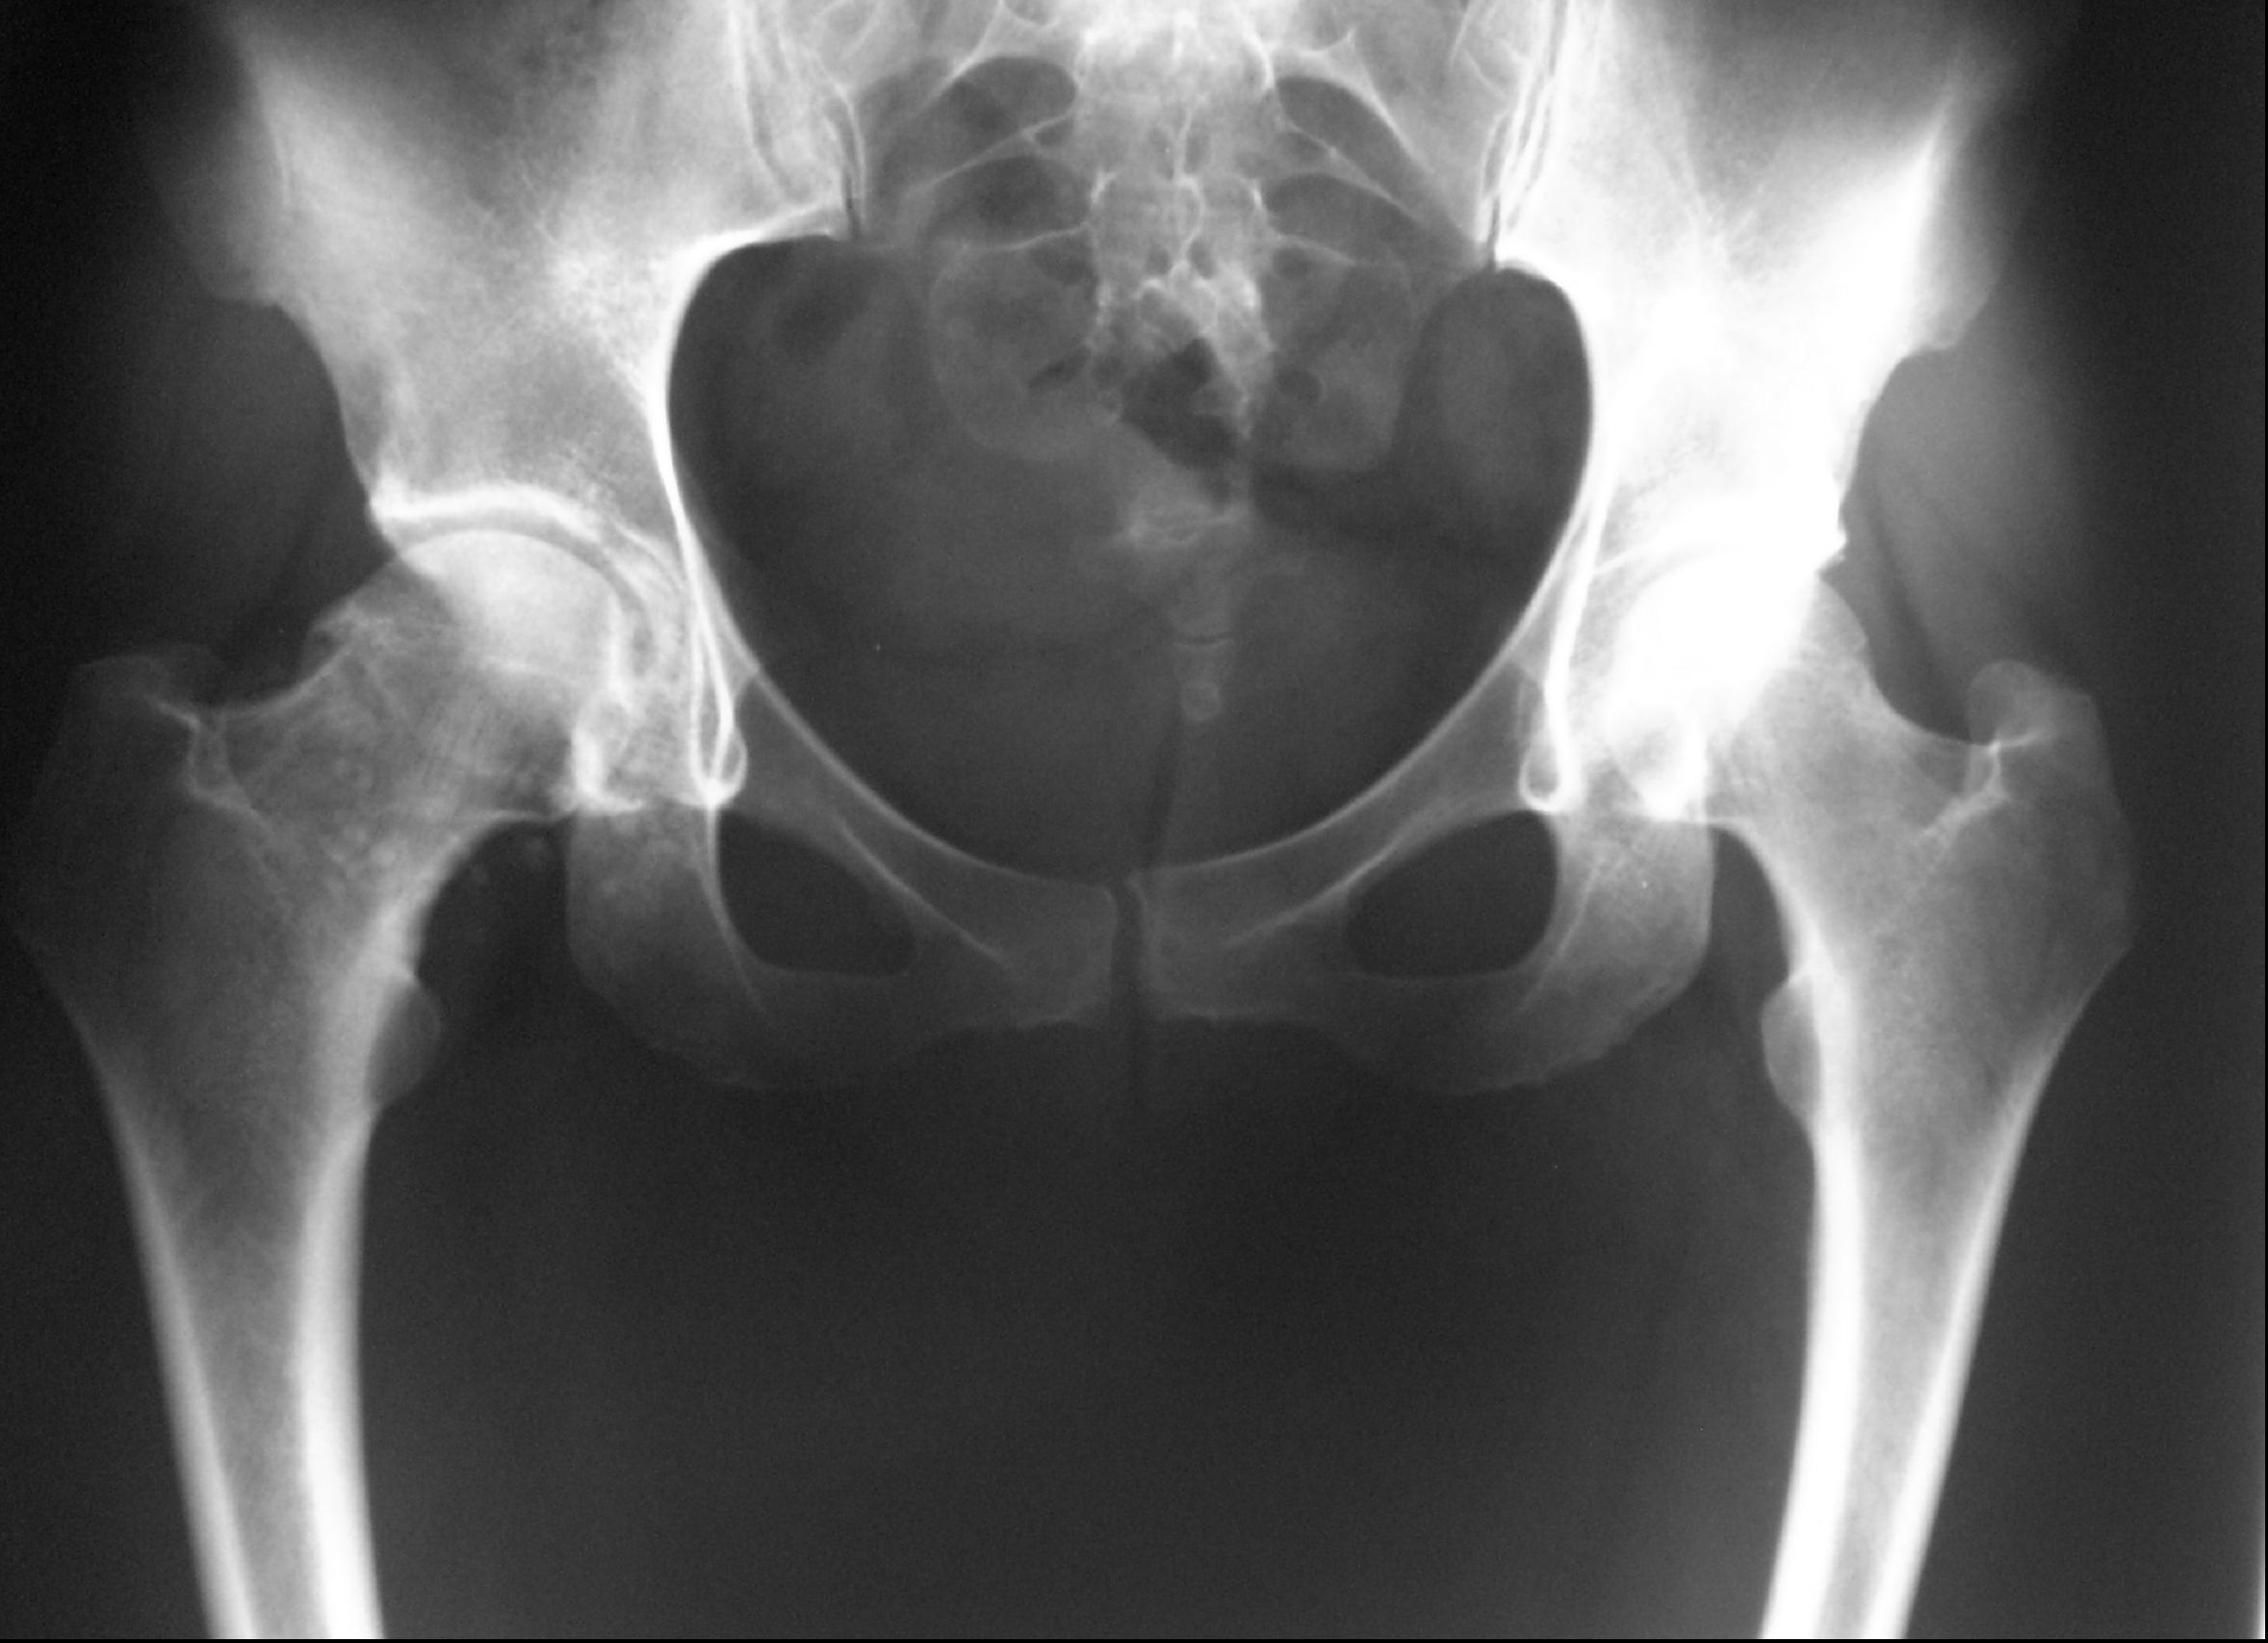

Condromatosis sinovial de Cadera. Tratamiento Artroscópico. [Hip synovial chondromatosis. Arthroscopic treatment.]